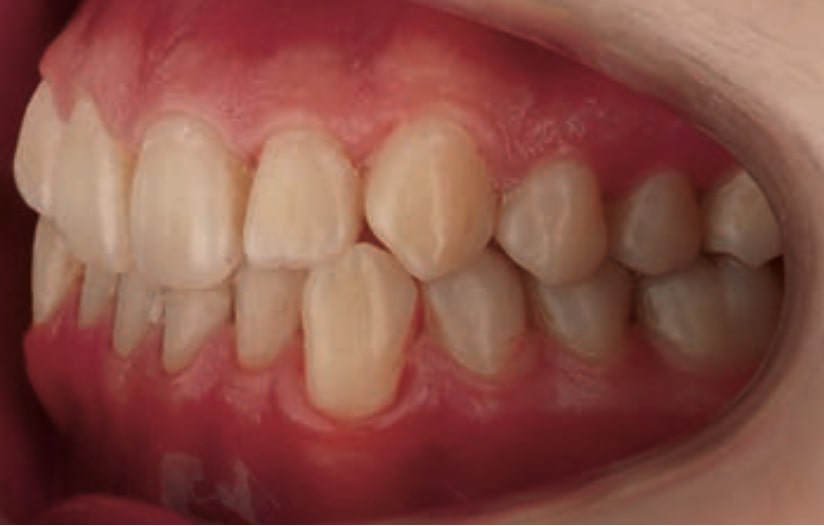

Chief complaint: The patient, a 19-year-old woman, was evaluated to undergo orthodontic treatment using the Angel Aligner Pro system. She presents with a skeletal Class III, mesofacial, with a dental Class III malocclusion and a 2 mm deviation of the lower midline to the left. Teeth 33 and 43 are out of the arch and cortical bone, with a crossbite issue on tooth 33. Fortunately, no functional issues affecting swallowing or breathing have been detected. The patient’s motivation for starting treatment was a general review of her dental and aesthetic health. The soft tissue analysis reveals mandibular protrusion that influences her facial profile. This diagnosis highlights the need for a comprehensive approach to address dental and skeletal misalignments, improving both the patient’s functionality and facial aesthetics.

- Dental Class III, 2 mm deviation of the lower midline to the left. 33 and 43 out of the arch and the cortical bone.

- Crossbite of 33.